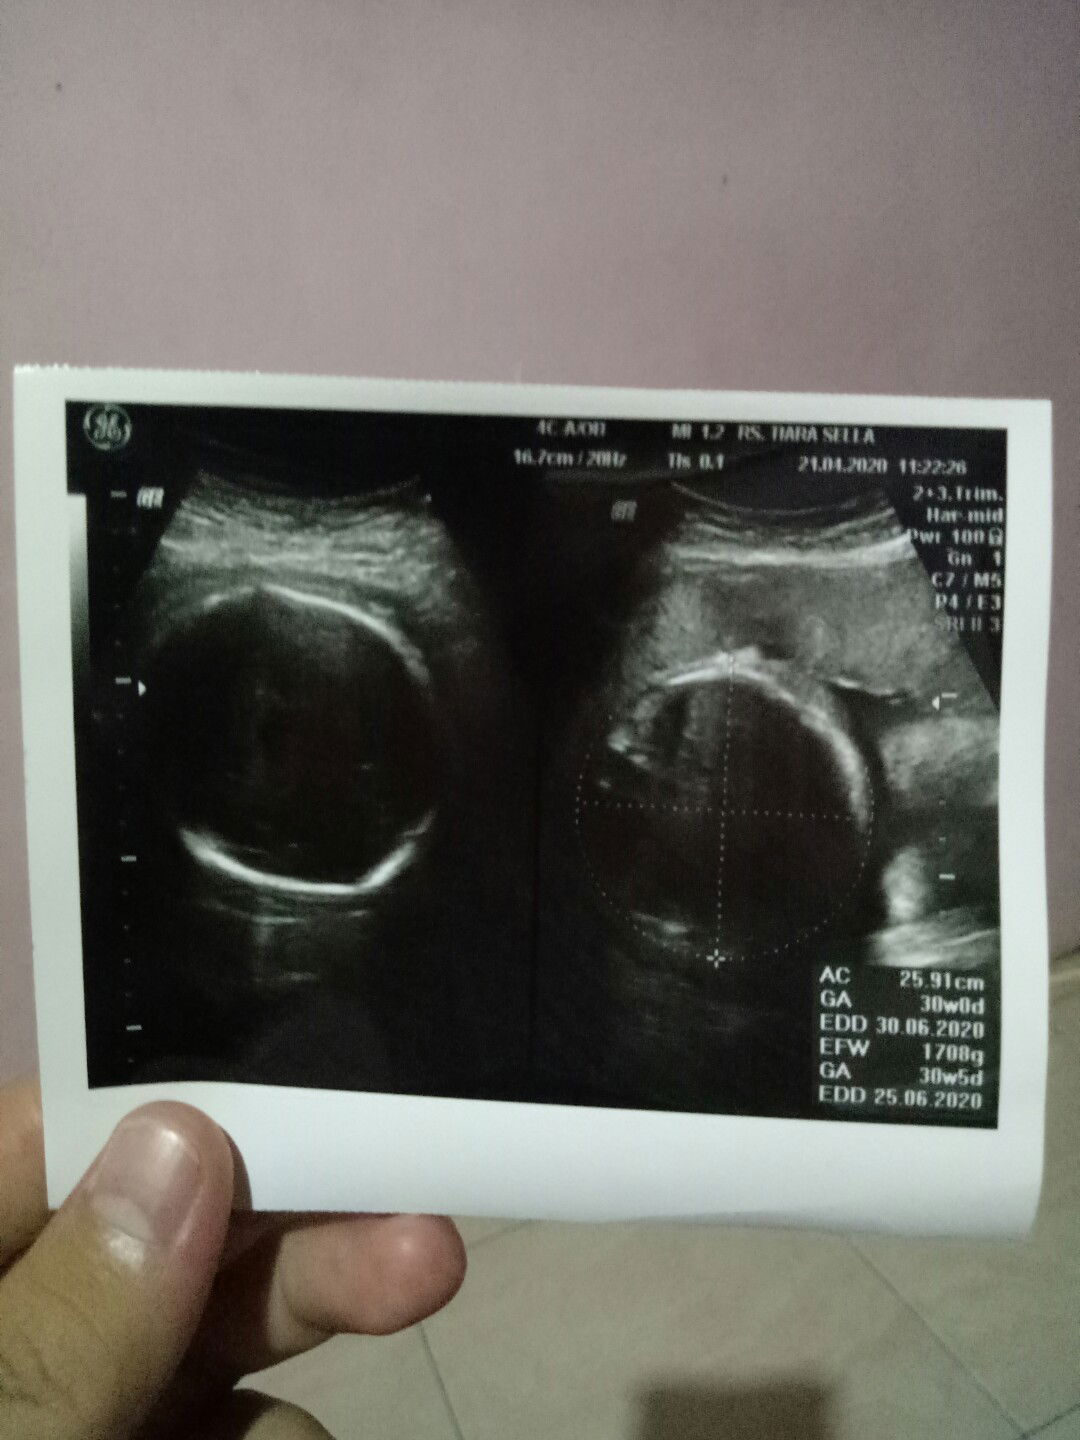

Bunda, aku kemaren abis cek ke dokter, dan usia janin ku skrg 30w6d. Nah yg jd pertanyaan ku, kemaren ke domter spog nya cuma usg doang. Bentar bgt malahan. Alhamdulillah normal katanya. Tapi kok ngga dkasih obat atau vitamin ya bun ?? Aku tanya ke susternya, ini pake tebus obat ngga sus ? Katanya engga bu. Trus aku tanya lg, emg udah ngga apa gimana. Katanya udah ngga bu, bnyak minum susu aja katanya. Menurut bunda* dsini gimana ? Apa iya kita udah ngga dkasih vitamin lg setelah janin umur sgini ?? Atau gimana Mohon infonya bun, maklum baru anak pertama bun

30W5D

Bun dsini ada yg asi nya udah keluar blm di sekitar 30W ??? Soalnya aku liat postingan bunda* ada yg 26w udah keluar asi nya. Sdngkan aku udh 30w5d tp blm ada tanda* asi mau keluar nih bun ? Aku blm paham apa*, soalnya ini jg baru anak pertama. Tp kata dokter td soal perkembangan janinku, alhamdulillah semua normal bun. Menurut bunda gimana ? Ada ngga yg asi nya blm keluar juga, trua gimana cara ngatasinnya ?

HPL maju mundur

Bun aku mau tanya, td aku baru aja cek ke dokter lg, terakhir aku cek bulan februari kemaren, dan HPL nya tgl 20 juni. Tp td pas aku cek lg, kok HPL nya mundur lg ke tgl 25 juni ? Emang nya bisa kaya gitu ya bun ??? Pertama tau cek dlu HPL nya tgl 25 juni, yg kedua tgl 21 juni, yg ketiga tgl 20 juni, trus tadi cek terakhir itu tgl 25 juni. Menurut bunda gimana ? Emang kaya gitu atau gimana ?? Maklum aku baru hamil anak pertama bun ? butuh pengetahuannya bunnn